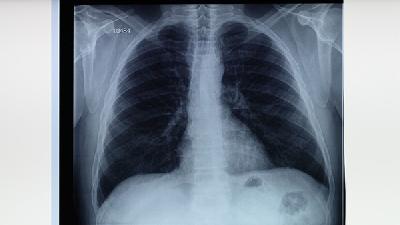

肺炎自查可关注咳嗽、发热、胸痛、呼吸困难等症状,早期表现为干咳低热,进展期出现脓痰高热,终末期可能伴随呼吸衰竭。...